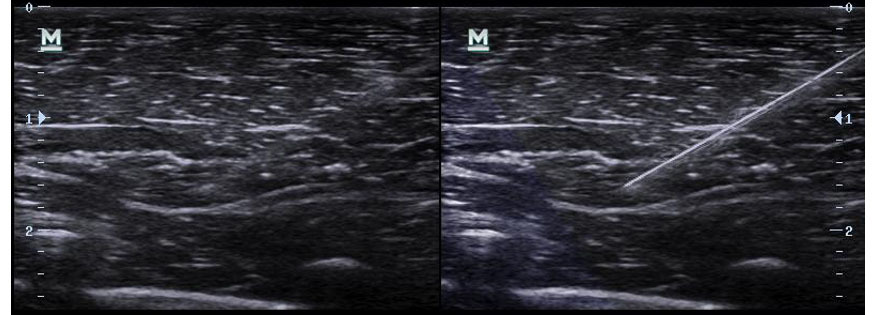

iNeedle™

Ваш инструмент для более глубокой биопсии: обеспечивает маневрирование УЗ-луча, чтобы улучшить видимость иглы, нервных волокон и мелких сосудов.